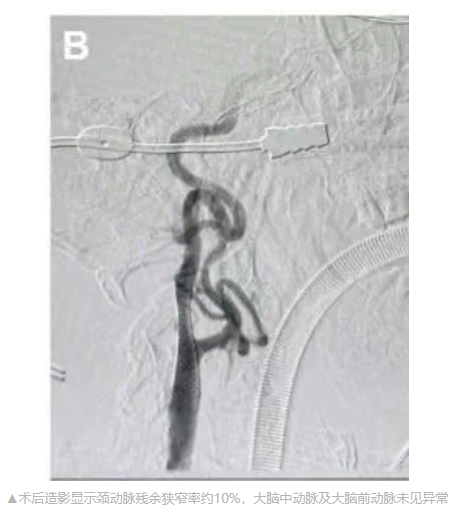

给予患者全身肝素化。造影提示右颈内动脉C1段重度狭窄,狭窄率约90%,颈总动脉长轴与颈外动脉夹角较大。通过交换技术,更换0.035in交换支撑导丝至颈外动脉远心端,经其将颈动脉-股静脉逆流管路系统放置在颈总动脉近端。夹闭颈总动脉近心端后,将管路系统与股静脉回流鞘连接,确认无气泡后建立颈动脉-股静脉逆流通路。经管路系统近端Y型鞘送入0.014 in微导丝至颈内动脉C1段远端,经其送入5.0mm *30mm球囊扩张病变。撤出球囊,放置9.0mm*30mm自膨式闭环颈动脉支架,完全覆盖病变。撤出微导丝及支架推送系统后,继续维持颈动脉-股静脉逆流2min。松开颈总动脉阻断夹,术中颈总动脉夹闭时长9min。造影显示颈动脉残余狭窄率约10%,大脑中动脉及大脑前动脉未见异常。撤出管路系统,荷包缝合颈总动脉穿刺点,逐层缝合颈动脉创面。